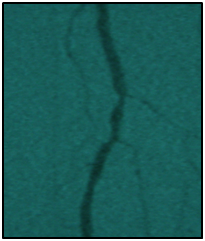

Endovascular procedure was done with antegrade access in the ipsilateral common femoral artery, diagnostic angiography confirmed: Patency of the femoral-popliteal axis, occlusion of the posterior and anterior tibial arteries, two critical stenotic lesions in the fibular artery and revascularization of the dorsalis pedis and plantar arteries by the fibular artery. To treat the fibular critical atherosclerotic lesions were performed a percutaneous transluminal angioplasty using a 0.0018in.guidewire, catheter support and a catheter balloon (3,0x6 mm and 3,5x 15mm).

Final angiographic control showed patency of the fibular artery and dorsalis pedis, with direct flow for the first metatarsal artery, thus guaranteeing enough flow to heal the ulcer in six months after the procedure. In conclusion endovascular treatment has a high technical eligibility with good reported outcomes and represents an alternative for diabetics with CLI Disease (Figure 1 and 2).

• Figure 2 From left to right showing percutaneous transluminal BTK balloon angioplasty, and revascularization of the dorsalis pedis and plantar arteries by the fibular artery.